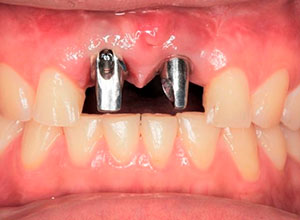

Nótese la colocación de los postes y el respeto a la forma de los tejidos gingivales y las papilas, muy importante para obtener el resultado estético final.

Colocación de postes rectos o angulados

Nótese el manejo de las zonas papilares

Provisionalización para el manejo de tejidos blandos